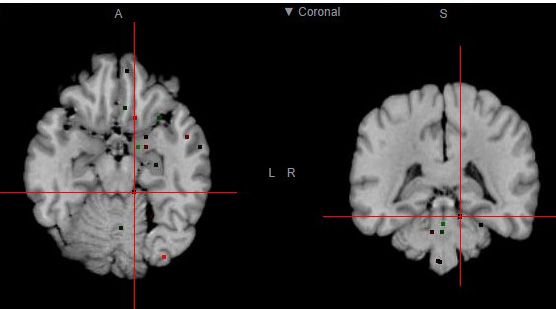

We will be discussing how we can combine genetics, pharmacology and neuroimaging to better understand the physiology underlying social cognition and the etiology of schizophrenia.

A general background of methodology and findings will be presented, and recent work from our lab at iMM Lisboa will be exemplified.